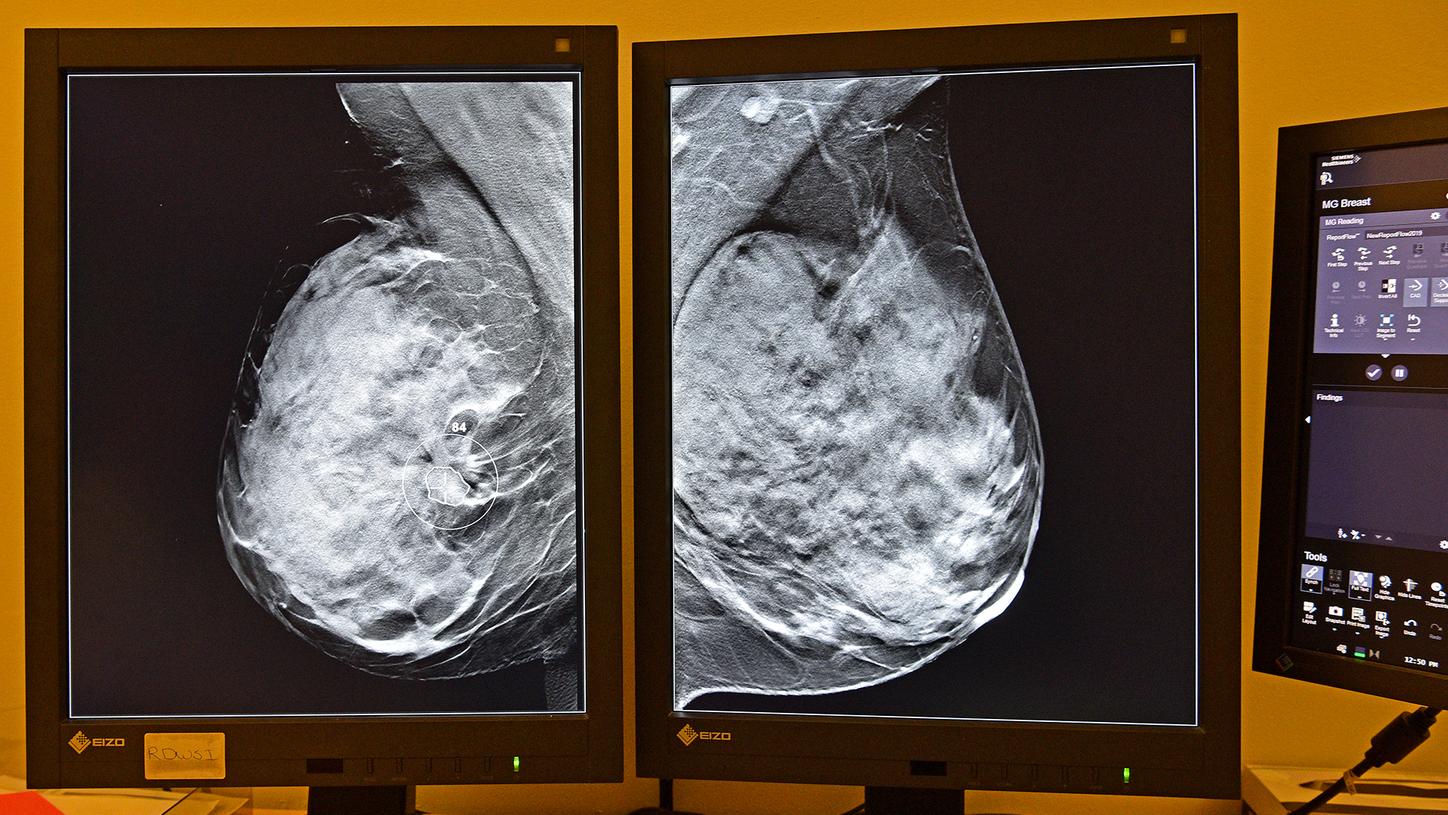

Artificial Intelligence enhances breast cancer screening

Artificial intelligence offers radiologists smart support in breast cancer screening

In breast cancer screening programs, such as the one running in the Netherlands, a high volume of mammography data is acquired. Radiologists have to evaluate hundreds of images every day with precision and often under time pressure. Artificial intelligence (AI) offers radiologists smart support: “It’s like having an additional colleague at the press of a button,” says radiologist Ritse Mann of Radboud University Medical Center, Nijmegen, the Netherlands.